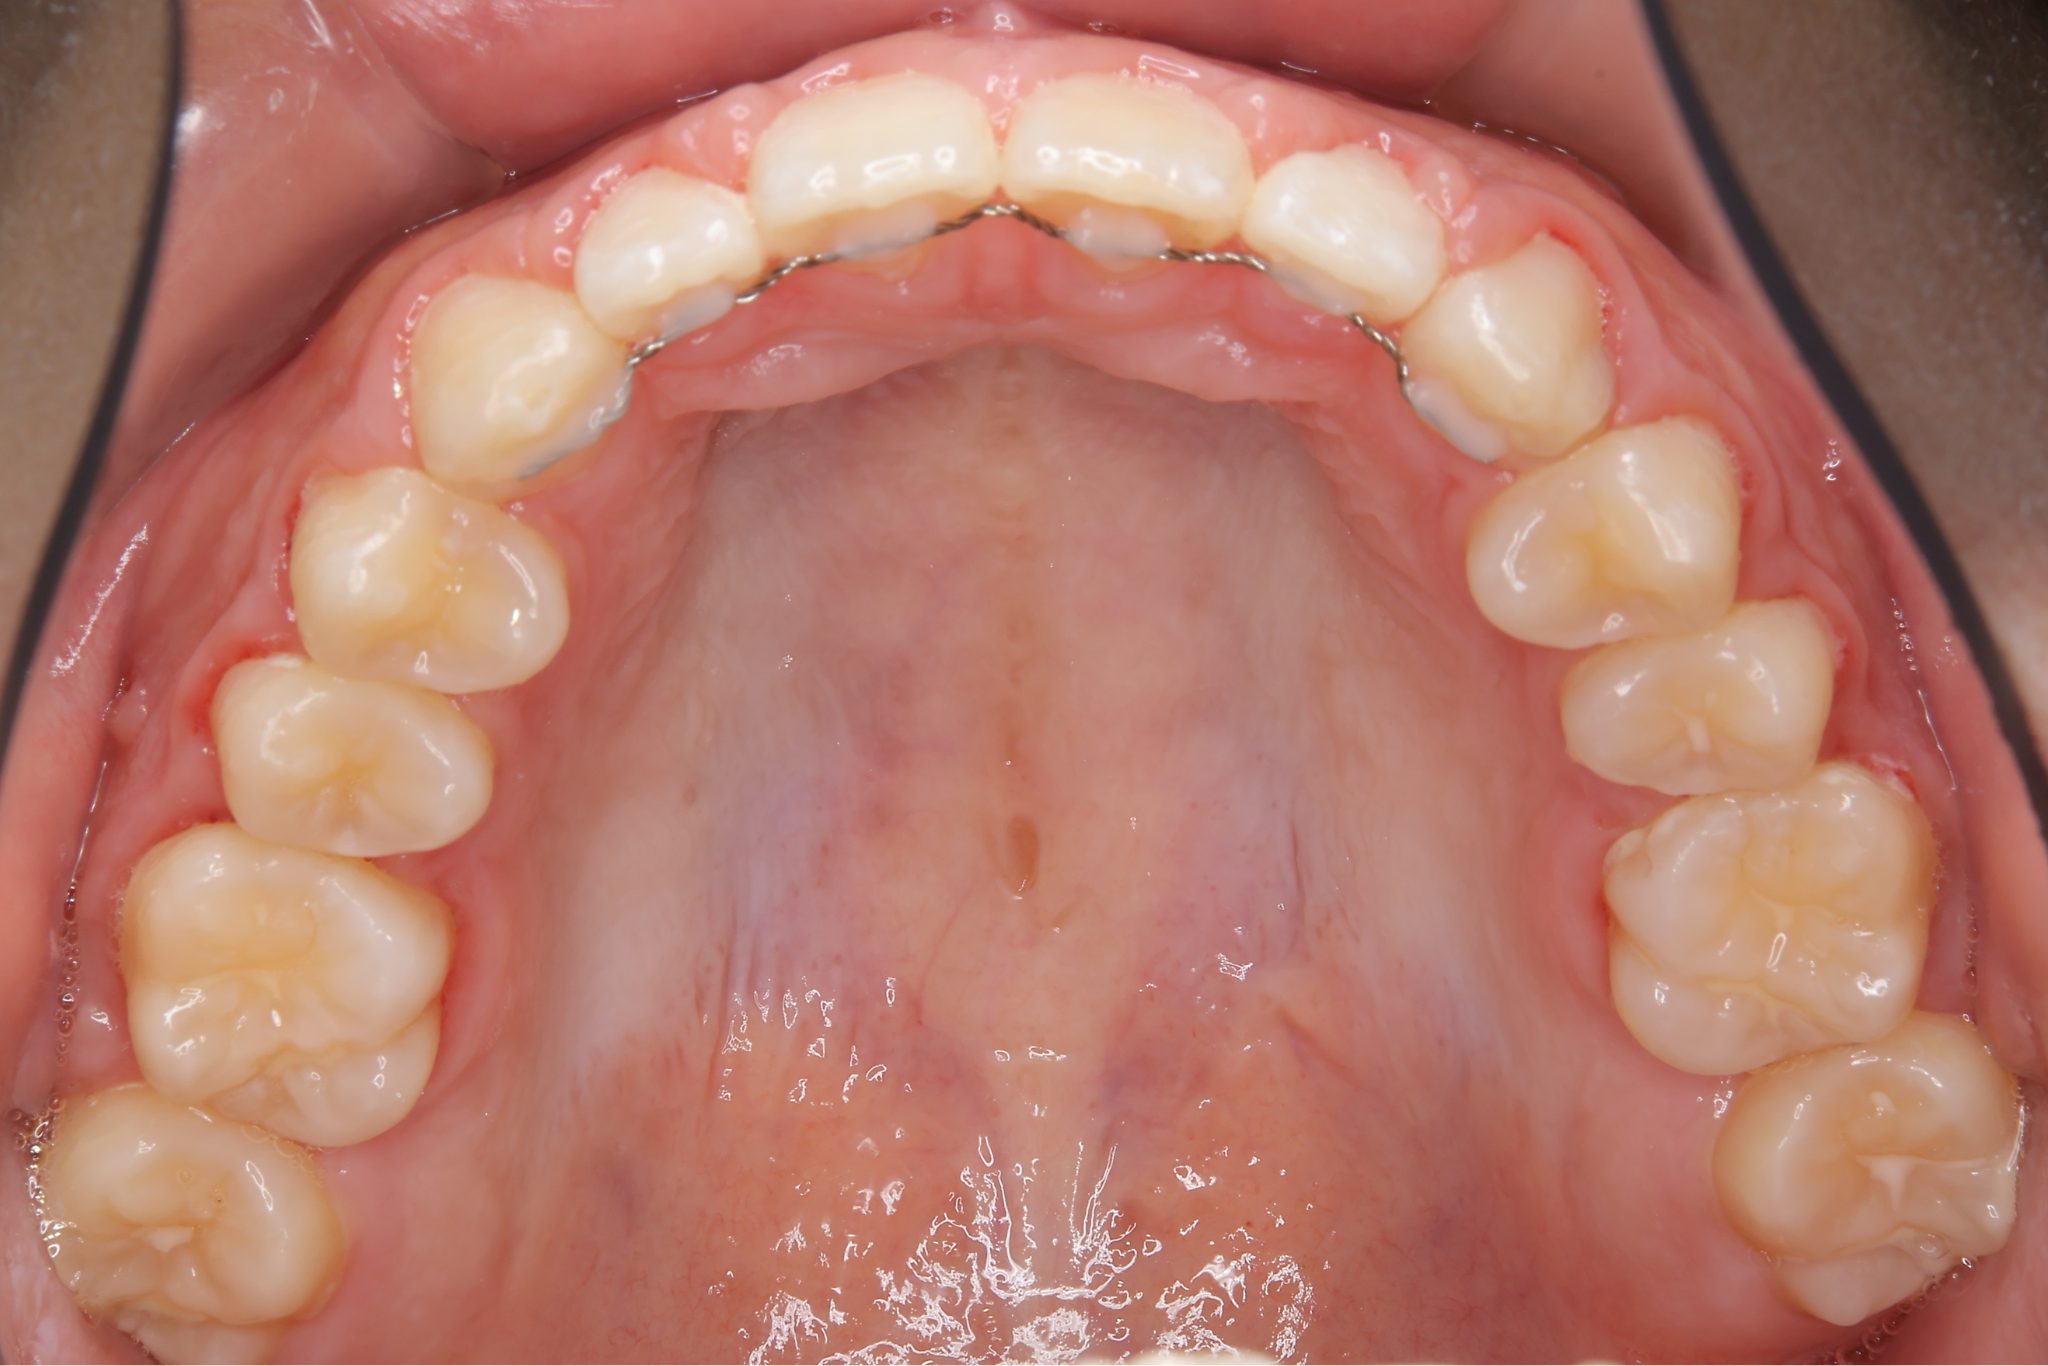

ビフォー

ワイヤー矯正治療|症例_681

主訴 上前歯が出ている|よく口が開いている

施術内容 上顎急速拡大装置と下顎リンガルアーチを用いて上下顎骨を拡大した。

その後マルチブラケット装置を用いて

非抜歯で歯牙を配列し良好な咬合を獲得した。

鼻閉症状は改善した。

治癒期間 2年10か月間